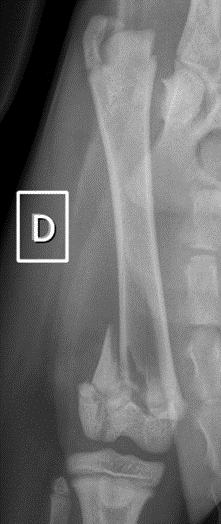

On trouve les cartilages de croissance chez les chats de moins d’un an, aux extrémités des os des pattes. Les cartilages de croissance permettent la croissance des os. Les cartilages de croissance sont plus fragiles que l’os proprement dit, et de ce fait plus souvent sujets aux traumatismes.

Le cartilage de croissance est une zone fragile de l’os donc plus susceptible d’être endommagée.

La classification de Salter-Harris des fractures du cartilage de croissance, décrite en médecine humaine donne une indication pronostique : une fracture Salter-Harris de type 1 aura un meilleur pronostic que le type 5. Toutefois, l’âge de l’animal au moment de la fracture et l’implication de l’articulation dans la fracture sont également très importants.